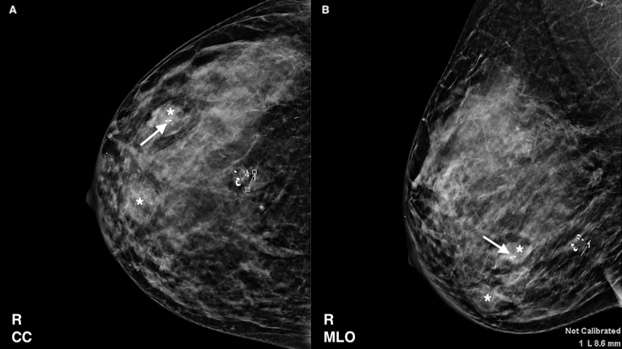

Figure 2. A 50-year-old female presents for routine screening mammogram with history of several circumscribed breast masses. A 9 mm oval mass in the right breast 6:00 position demonstrates coarse peripheral calcifications in a pattern consistent with “popcorn calcifications”, essentially diagnostic of a benign fibroadenoma (A, B). Additional scattered circumscribed breast masses are also noted (asterisk), including a biopsy proven benign mass in the inferolateral breast with a microclip (arrow).